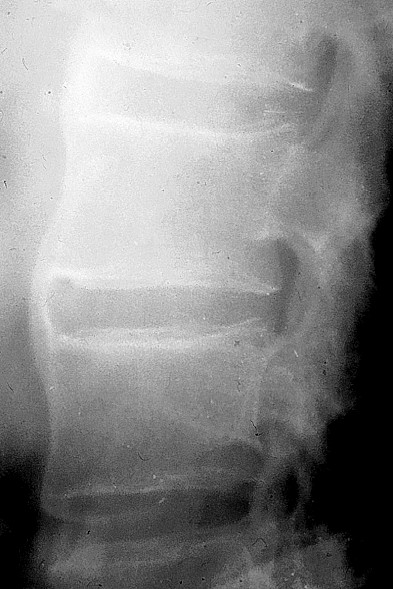

Les signes de rhumatisme inflammatoire périphérique se traduisent au début par un simple gonflement des parties molles (synovite) puis par une déminéralisation métaphysoépiphysaire « en bande », des érosions épiphysaires, un pincement irrégulier mais global de l’interligne articulaire et des géodes souschondrales (destruction articulaire) (figure 1.2).

Fig. 1.2. Aspect radiographique de polyarthrite rhumatoïde. Érosions rhumatoïdes caractéristiques des articulations des doigts traduisant l’agressivité de la synovite rhumatoïde